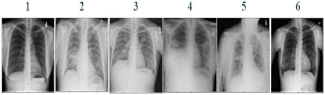

Furthermore, six chest X-ray (CXR) images were selected from the Nation Institutes of Health Chest X-ray Database (Nation Institutes of Health, Clinical Center, Bethesda, MD, USA) [46,47,48] for validating the proposed cryptography mechanism (Table 2). Six images were labeled as representing normal condition, pneumonia, fibrosis, pleural effusion, emphysema, and pneumothorax, respectively, and each image in portable network graphics (PNG) format was digitized to a resolution of 96 × 96 dots per inch and 24 bits per pixel (colored image), and was a 1024 × 1024-pixel image. They were resized from 1024 × 1024 pixels to 227 × 227 pixels in JPEG format. As seen from the results of the correlation and histogram analyses in Figure 9, the linear regression method showed a low correlation in the cipher image, being CC = 0.9063 for the plain image in Figure 9a and CC = 0.1338 for the cipher image in Figure 9c, respectively; the histograms were significantly different for the cipher and plain images (Figure 9b,d). The average NPCR, UACI, and IE of 100.00%, 51.87%, and 7.4428, respectively, could be obtained to indicate the significant potential of the proposed method for CXR image encryption. In the decryption process, the average SSIM and PSNR of 0.9319 and 104.5048 dB, respectively, were obtained to measure the recovery quality of the decrypted images, offering promising recovery quality for the existing medical imaging examinations of cardiopulmonary diseases and lung cancers. The experimental results of the six selected CXR images are shown in Table 2. Additionally, with a standard digital image (512 × 512 pixels in tagged image file format, 96 × 96 dots per inch and 24 bits per pixel) from the University of Southern California-Signal and Image Processing Institute (USC-SIPI) Image Dataset [48,49], Figure 10 indicates the satisfactory encryption performance of the proposed method using correlation and histogram analyses. With 100 children’s headshots [36], 10 hand X-rays, 20 CXR images [46,47,50], and 10 standard images [49], Table 3 shows the experimental results for the image encryption and decryption evaluations. The experimental results validated the performance of the proposed cryptography mechanism and its encryption and decryption abilities. In Table 4 is shown comparison of different cryptography mechanisms for digital image encryption.

Figure 9.

Correlation analysis and histogram analysis for chest X-ray images. (a,c,e) Correlation analysis for plain image, cipher image, and decrypted versus plain image, respectively; (b,d,f) histogram analysis for plain, cipher, and decrypted images, respectively.